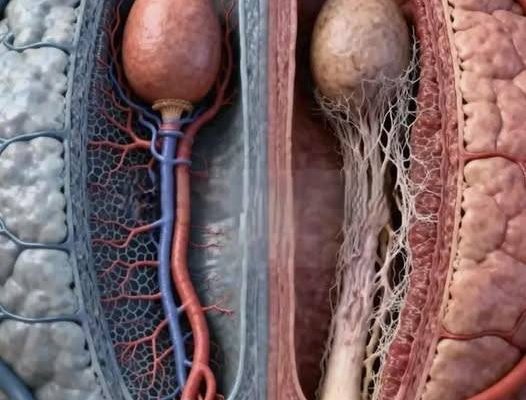

Visually and structurally, younger tissue tends to be denser, more elastic, and better supported by blood vessels, while older tissue may appear thinner, less compact, and with reduced vascular support—completely natural changes that help explain differences in physical experience over time.